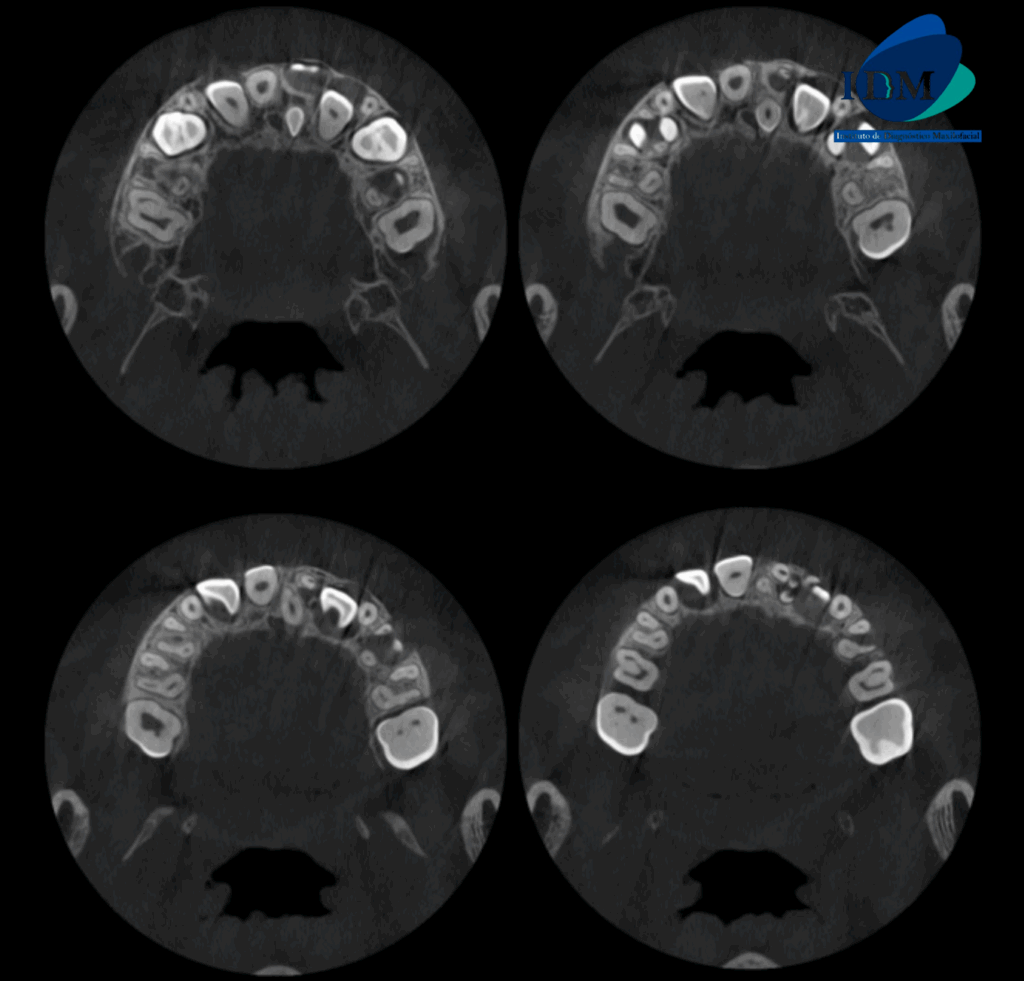

En la radiografía panorámica (Figura 1), se aprecia imagen radiopaca circunscrita con un halo radiolúcido proyectado sobre el tercio medio radicular de pieza 61 y tercio apical de pieza 73.

Radiografia Panorámica

A la evaluación de la tomografía volumétrica (CBCT) en los cortes axiales (Figura 2) y transaxiales (Figura 3), se aprecia pieza supernumeraria en posición invertida localizada hacia palatino de pieza 21, segmento coronario mesial en contacto con la cortical de conducto nasopalatino. Asimismo, se observa imágenes hiperdensas circunscrita por un halo hipodenso localizado adyacente a cima del reborde alveolar a nivel de pieza 21, que ocasiona desplazamiento de pieza 21 hacia vestibular.